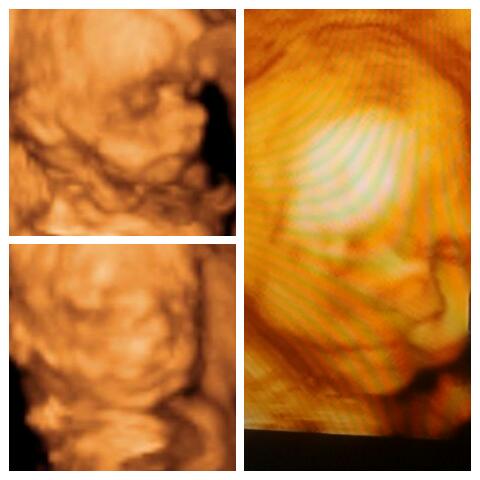

my johnitoo .. cant wait to see u here #happymommy